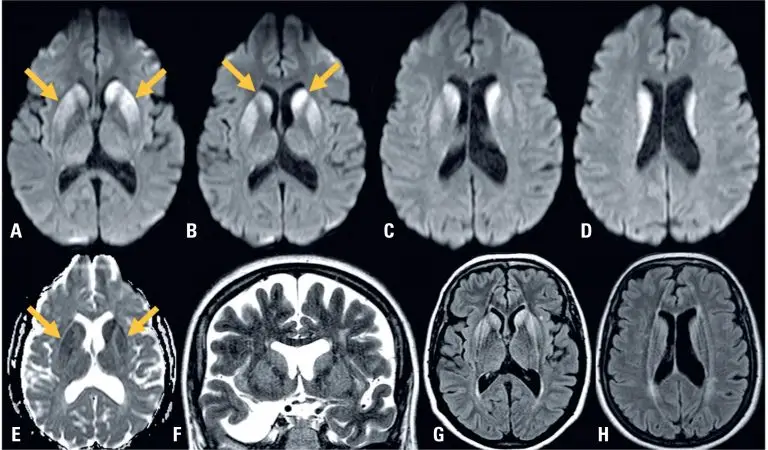

Stiff-person syndrome (SPS) is an autoimmune disease classically characterized by progressive muscular stiffness and lower back pain with sudden episodes of muscular spasm and, in certain cases, dysautonomia.() In general, the disease is diagnosed based on the presence of high anti-glutamic acid decarboxylase (anti-GAD) antibody titers both in the serum and cerebrospinal fluid (CSF), axial muscle stiffness in the special abdominal and thoracolumbar paraspinal fluid leading to hyperlordosis, painful spasms with well-defined triggers, electromyographic evidence of continuous motor unit activity, […]